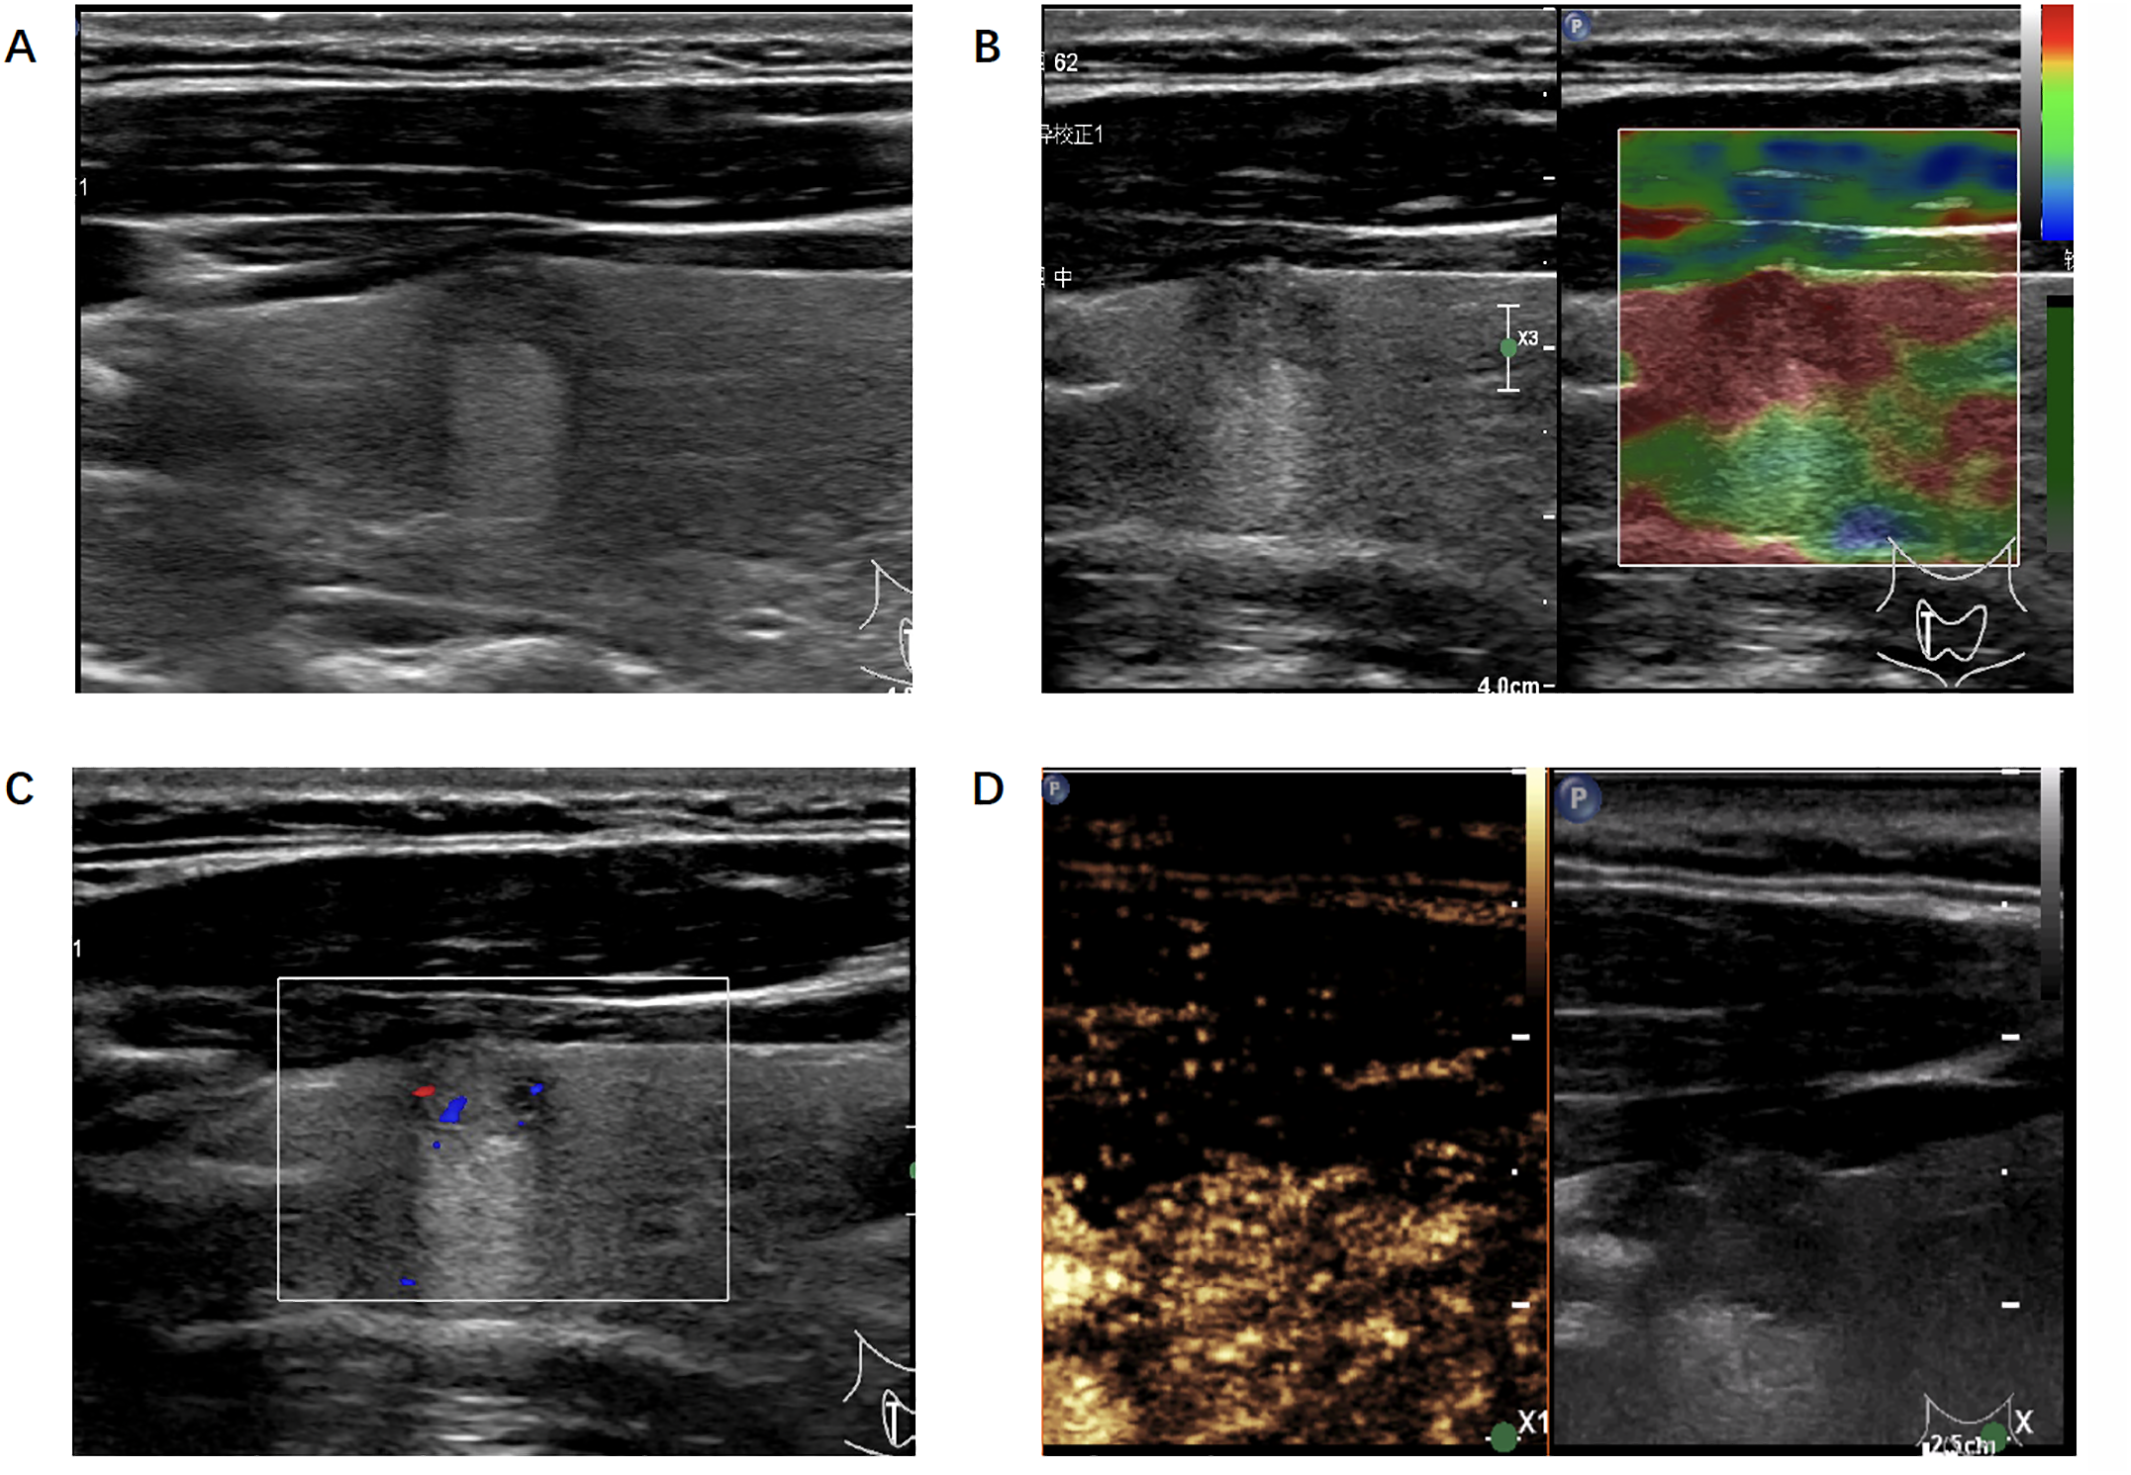

Figure 3

Ultrasonic image of the thyroid nodule which was misjudged by the radiologists but correctly predicted by the algorithm. (A) B-mode ultrasound showed a longitudinal section of the nodule. (B) Real-time elastography image of the nodule. (C) Color doppler flow image of the nodule. (D) The 30-second image of contrast-enhanced ultrasound in thyroid nodule.

In our study, we finally built 28 ML-based radiomics models and the AUC of the best model was 0.89 when inputting multimodality ultrasound imaging. In the same situation, the AUC of senior radiologists was 0.88 and 0.69 for junior radiologists. We showed a case where the radiologist was wrong but the algorithm predicted correctly (Figure 3). The diagnostic performance of the algorithm and radiologists for identifying benign and malignant thyroid nodules differed. What’s more, the addition of CEUS data improved their diagnostic performance, implying that thyroid CEUS cines carry substantial information that can be mined and analyzed.